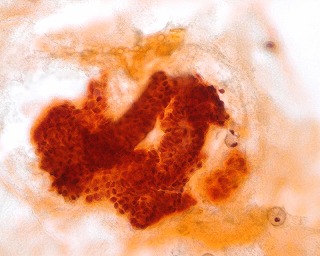

50歳代  女性  乳腺穿刺

*画像をクリックすると拡大写真が見れます。